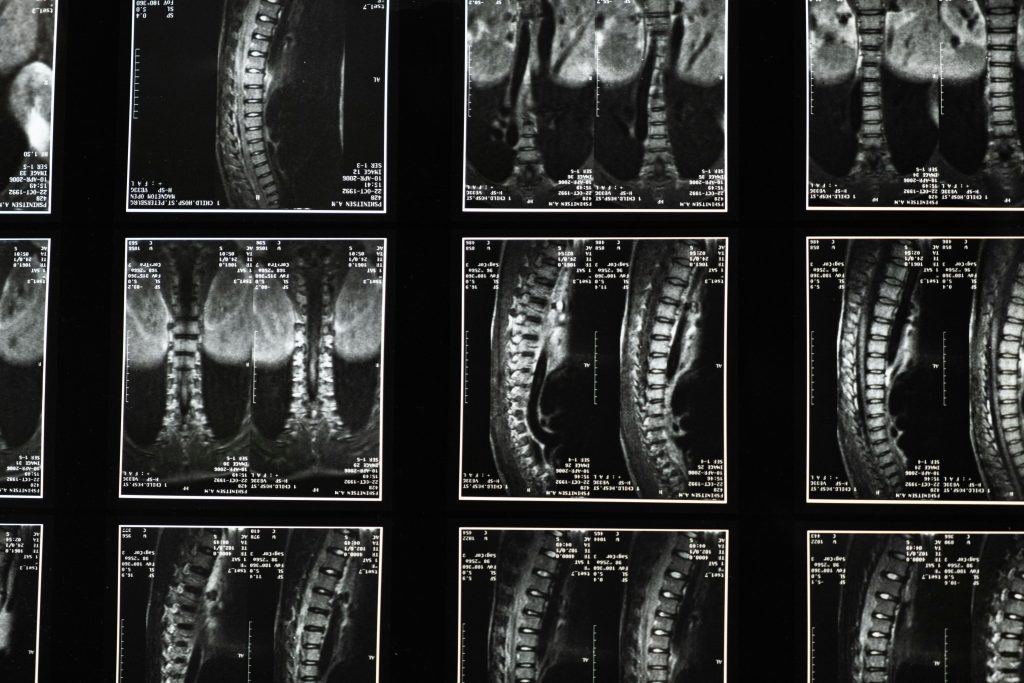

Experience the freedom from back and neck pain with our expert spine surgery services. Our team of skilled neurosurgeons specializes in the latest minimally invasive techniques to treat a range of spinal conditions, from herniated discs, stenosis, spinal tumors to spinal deformities like scoliosis. Spine and Brain Surgery Centre will help you regain your mobility and achieve the quality of life you long for